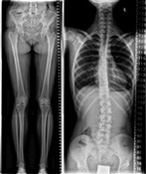

The orthopedic package is designed to allow you to do full spine and full leg imaging either on the vertical stand (equipped with the patient support), or simply at the table for lying or standing patients. Systems which are already configured with automatic image stitching at the vertical stand can now experience enhanced room flexibility by adding the automatic image stitching software for images acquired at the CombiDiagnost R90 table.

We are very satisfied with the image quality for both, spine and legs, when we use the stitching feature at the CombiDiagnost R90 table."